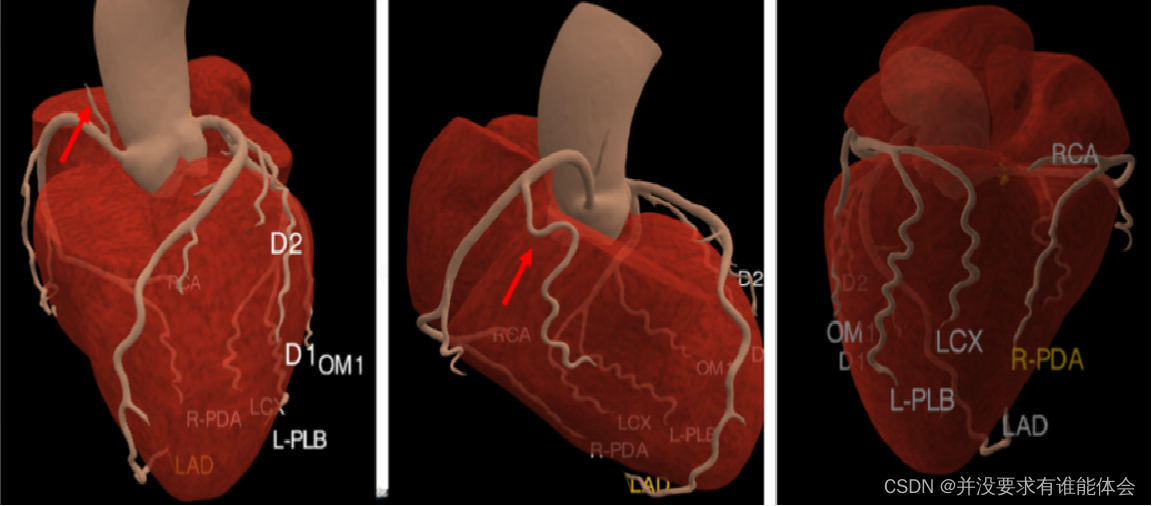

冠脉解剖-走形、分段

右冠状动脉:白右冠状赛发出后,行走于主肺动脉干和开主动脉根部间的右房室沟内,绕向心胜右后方再向左后走行,沿途发出圆锥支、实房结支、說缘支、后降支

圆锥支:第一分支,发自右冠状动脉最近端,供应右室的肺动脉圆锥。30%左右从主动脉发出;

实房结支:60%起自右冠状动脉,40%起自左冠状动脉;

税缘支:供应右心室前壁;

右后降支供应左心室下壁和房室结。

右冠分支

冠脉解剖

左冠状动脉主干:主要分为左前降支和左回旋支,直径分别为5-10mm和4-5mm。部分还发出中间支。

左前降支:由左冠状动脉主干向前下沿前室间沟行走于左、右心室间,远抵心尖部,在78%的心脏中折向心脏膈面的后室间沟与后降支吻合。主要向左心室游离壁、室间隔前上2/3及心尖部供血。沿途发出对角支和前室间隔支

左回旋支:呈近乎直角从左主干发出,沿左房室沟向左后行走至后室间沟。向左室侧壁,后壁供血。沿途发出钝缘支和左房旋支。

左冠分支

冠脉解剖-分段

第1段:右冠近段 (pRCA),右冠开口到锐缘支开口一半长度

第2段:为右冠中段(mRCA),其余到锐缘支开口处另一半的长度

第3段:为右冠远段(dRCA),右冠中段末端-后降支(PDA)开口

第4段:右冠起源后隆支 (R-PDA)

第5段:左冠状动脉主干(LM)

第6段:前降支的近段(mLAD):开口到第一室间隔支的开口

第7段:前降支的中段(mLAD):间隔支的开口到心尖部的-一半长度

第8段:前降支的远段(dLAD):前降支中段末端到前降支未梢

第9段:第一对角支(D)

第10段:第二对角支(D2 )

第11段:回旋支近段 (pLCX),回旋支开口处-钝缘支开口处

第12段:第一钝缘支 (OM1)

第13段:回旋支远段(dICX):钝缘支开口以远部分

第14段:第二钝缘支 (OM2)

第15段:回旋支发出的后降支 (L-PDA)

第16段:右冠起源后侧支 (R-PLB)

第17段:中间支(RI):起自LAD和LCX分叉处

第18段:回旋支起源后侧支 (L-PLB),后侧支起源于回旋支